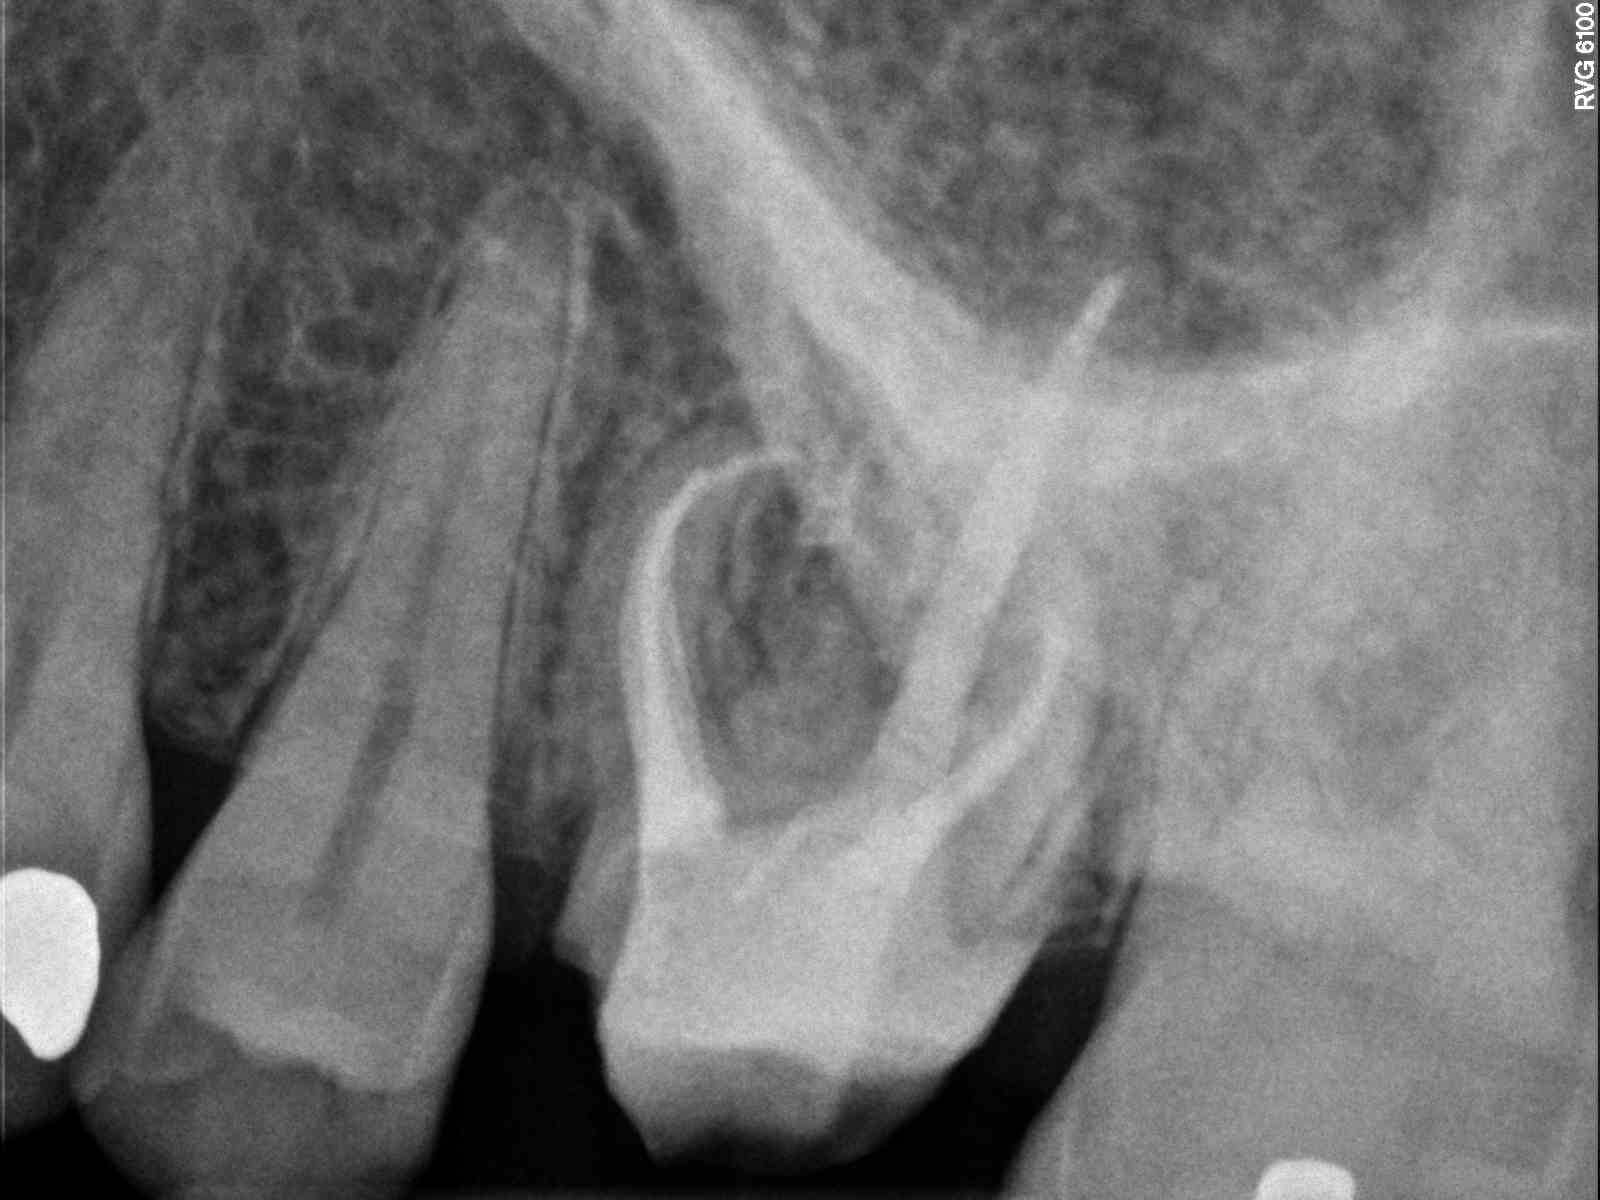

Not sure on this one as far as MB1 length. It appears MB2 and MB1 end at different lengths or I overfilled MB1 by .5-1mm (Kodak says .6mm) if i use the worst looking xray.

![]() |

| Here looks like it’s long |